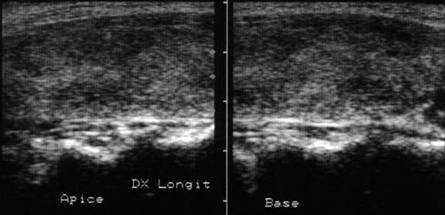

Apexul lobului drept, proiectie longitudinala si trasversala.

Femeie 58 ani. Maladia Graves in tratament cu

metimazol.

Nodul unic in apexul lobului drept, de 11x14x20mm (1,5 cc), hipoecogen, cu

contur difuz

Nu s-a efetuat citoaspiratie.